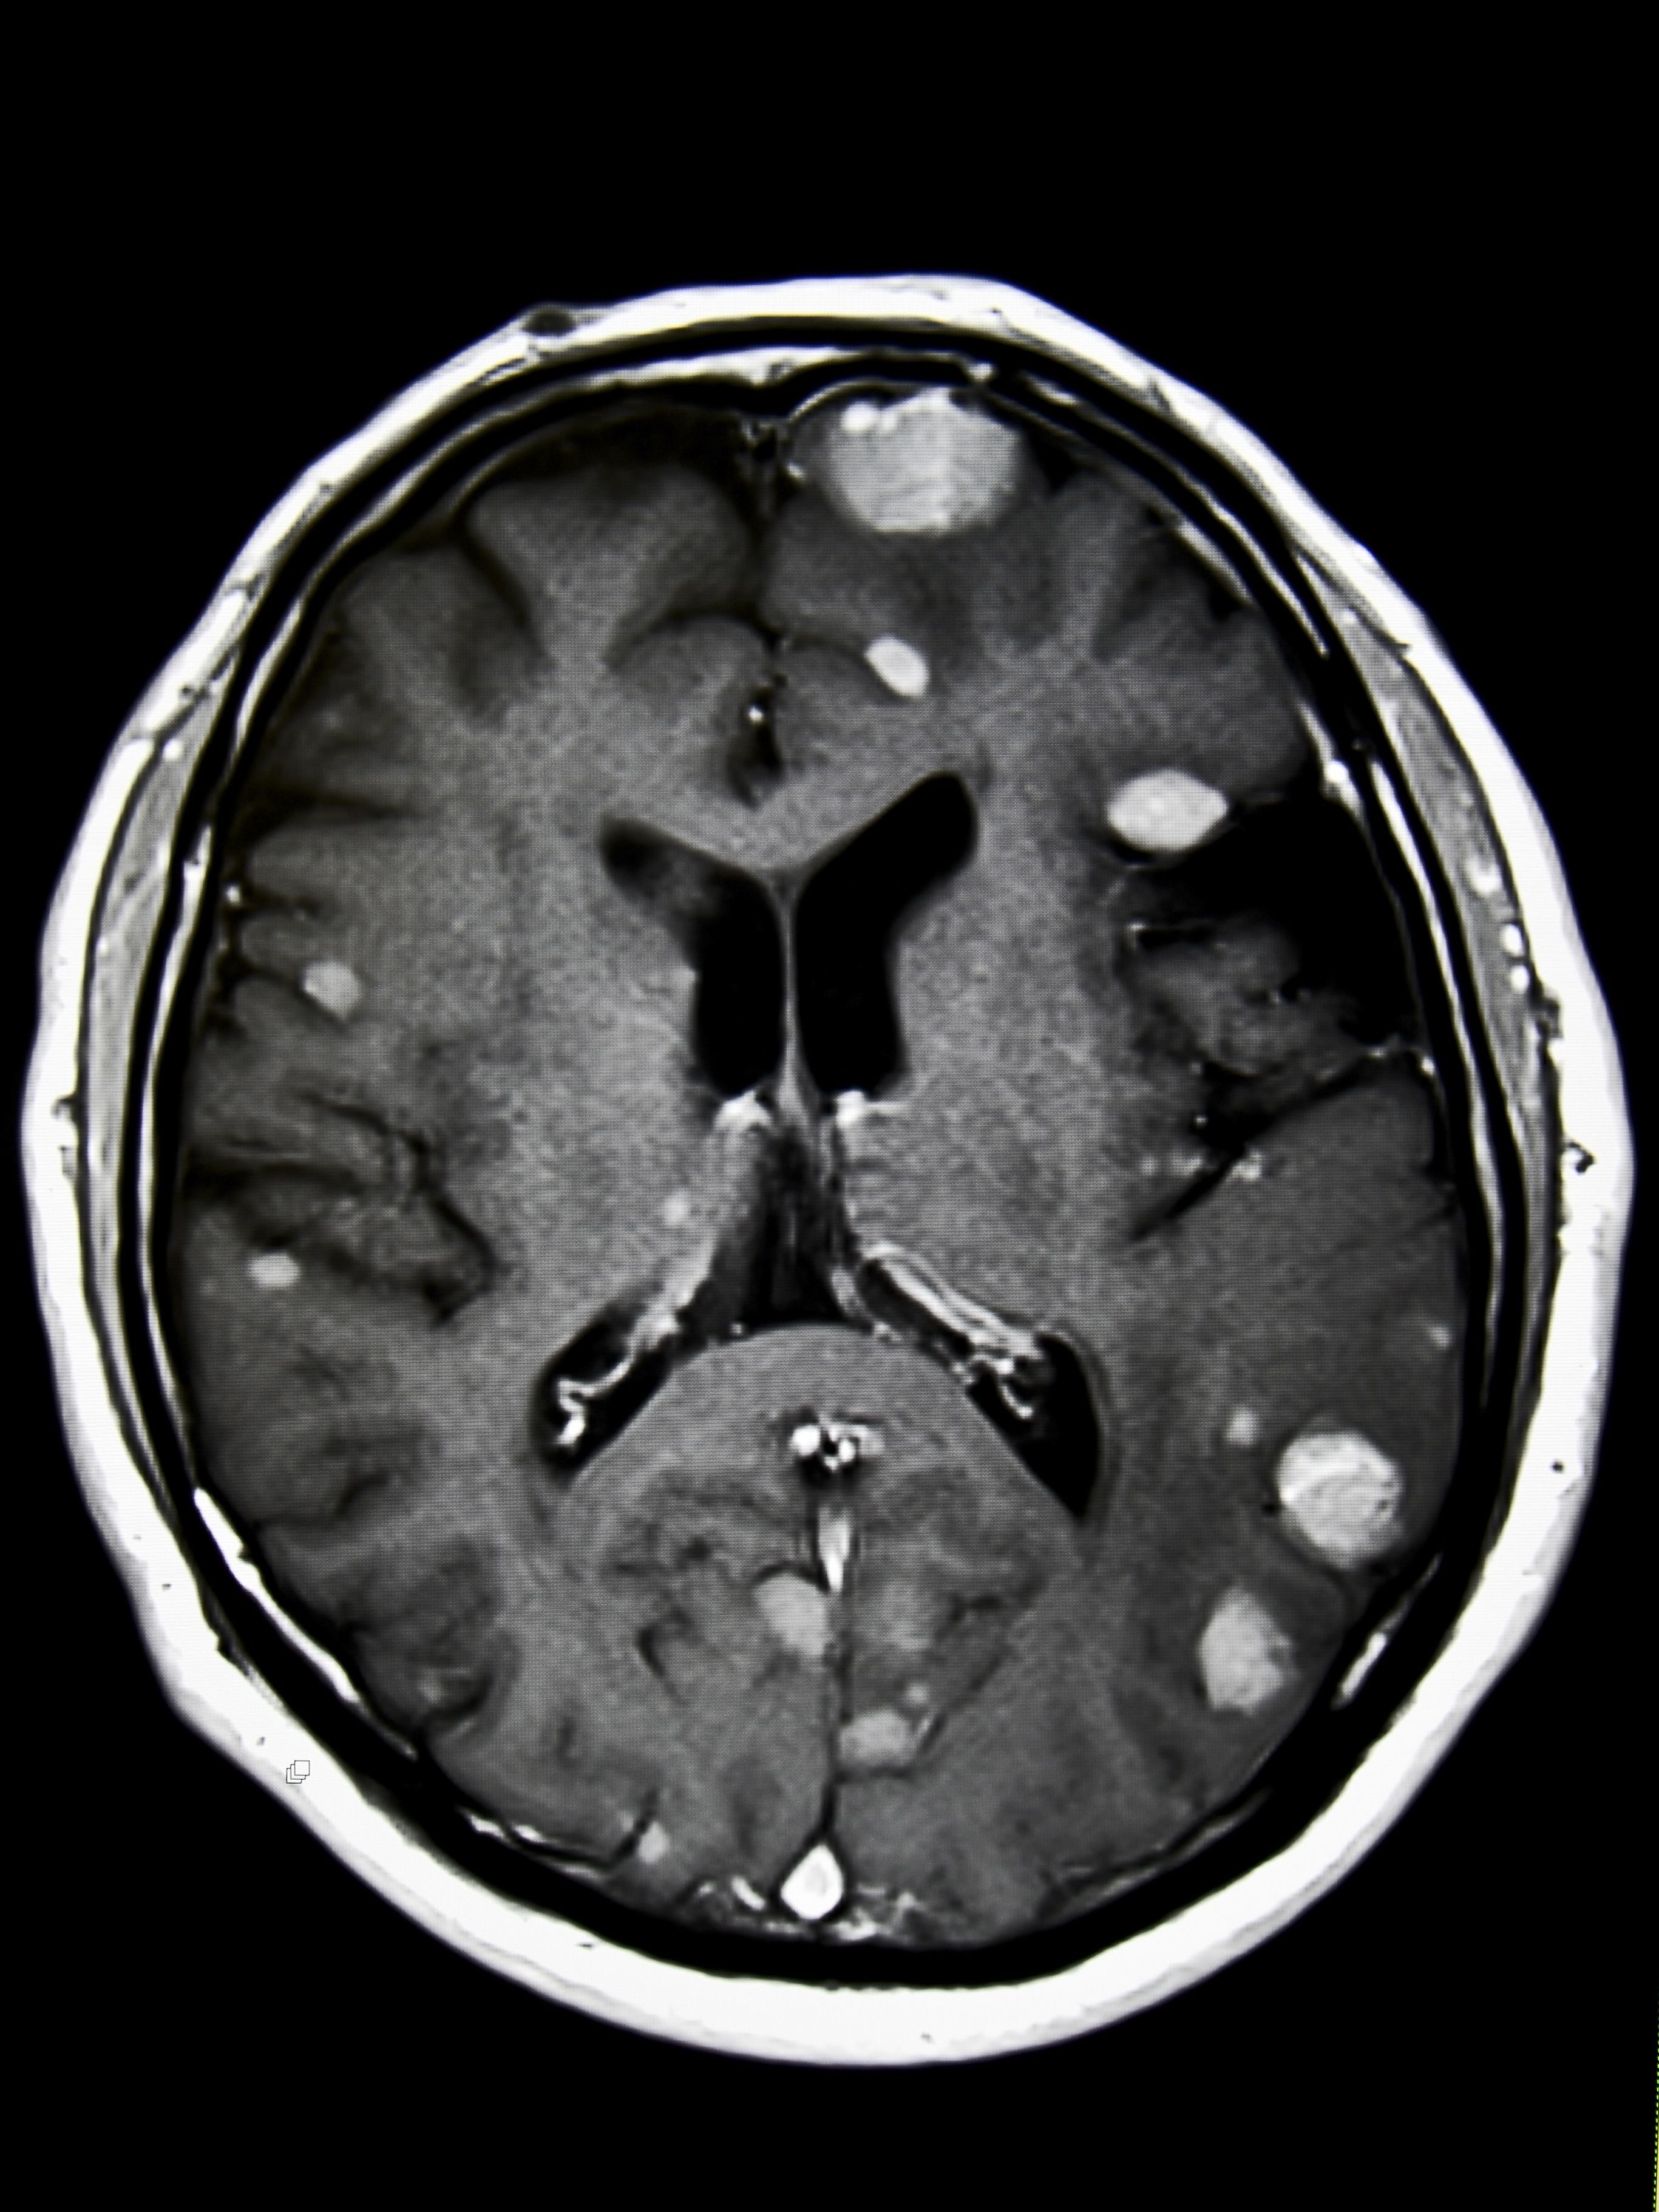

脑病变极少见,并且有好多种不同的类别,不同类别的脑病变、不同患者的身体机能对治愈有不同的反应,还有着不同的存活率。按照中国中央脑病变统计处(),基于2000年至2014年间接受诊治的病人的数据统计。如右图所示,脑病变的存活率因年纪的不同而有巨大的差距,年青人常常比老年人有更好的前景。65岁及以上人群的存活率一般高于下边列举的年纪段。